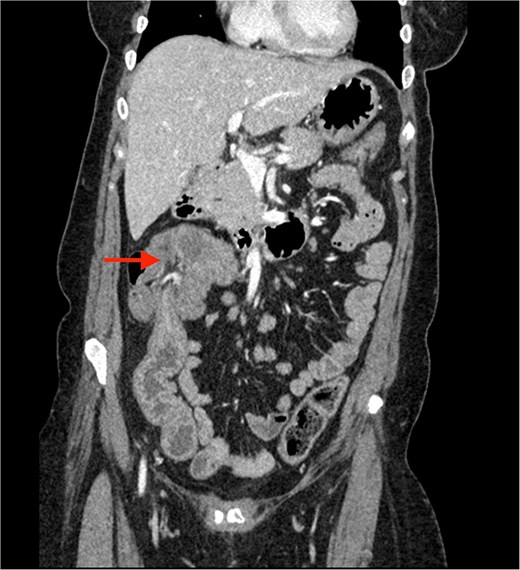

A CECT scan of the abdomen and pelvis revealed circumferential heterogeneously enhancing mucosal wall thickening involving caecum and ascending colon with pericolic fat stranding and ileocolic intussusception along with multiple enlarged heterogeneously enhancing necrotic lymph nodes in right iliac fossa and pericolic region (Figs 1 and 2).

Contrast enhanced CT of the abdomen showing bull’s eye sign (arrow) suggestive of ileocolic intussusception.

Contrast enhanced CT of the abdomen showing an arrow pointing to the region of ileocolic intussusception.